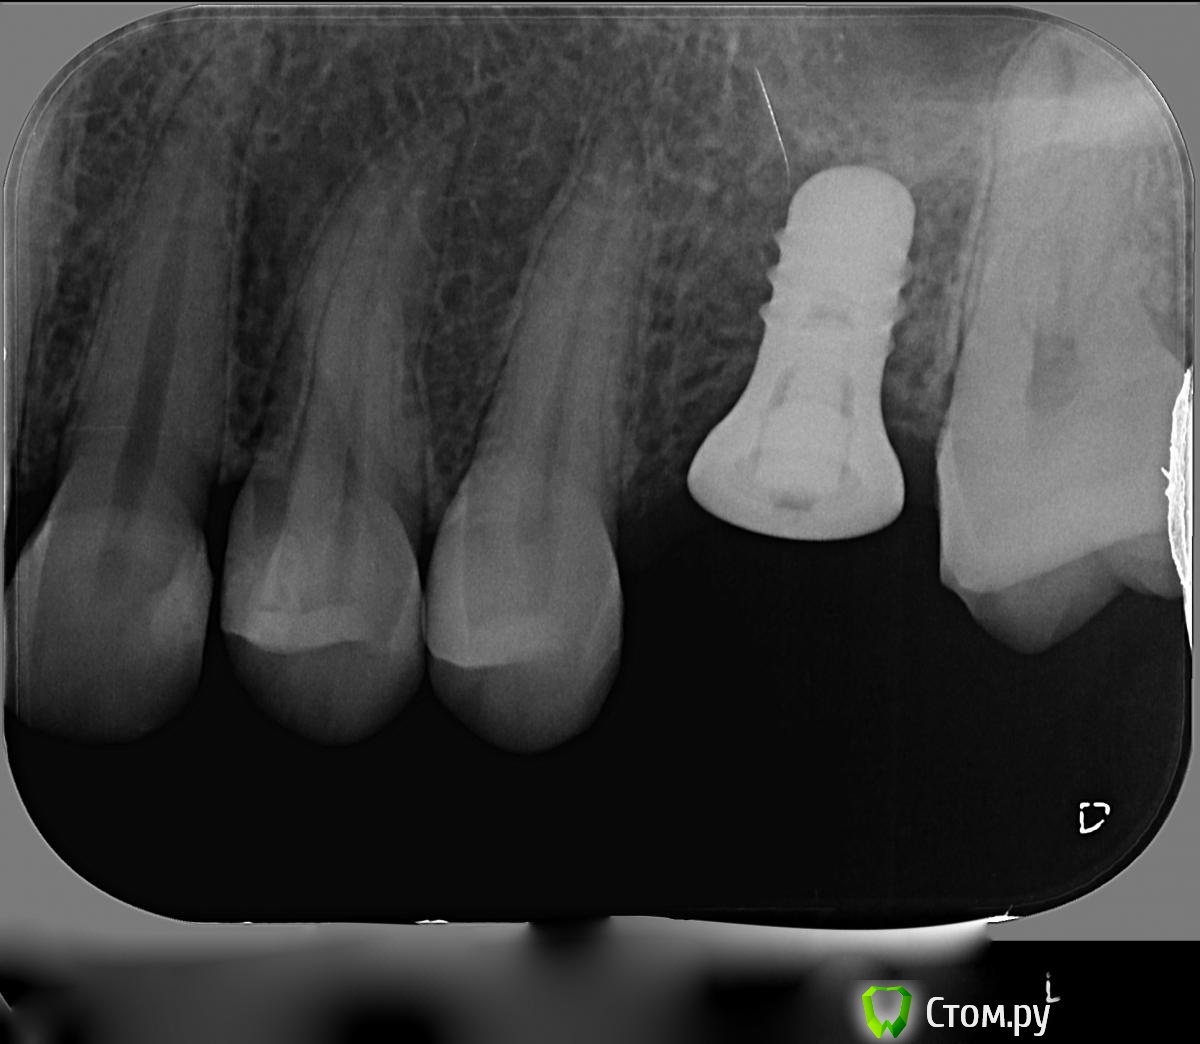

Korn05 Опубликовано 17 января, 2014 Автор Поделиться Опубликовано 17 января, 2014 (изменено) Свежий снимок. По словам врача, десна воспалена ближе к левому от импланта зубу (5-ке). Изменено 17 января, 2014 пользователем Korn05 Ссылка на комментарий

Korn05 Опубликовано 17 января, 2014 Автор Поделиться Опубликовано 17 января, 2014 (изменено) Еще: когда я нажимаю на десну прямо над имплантом, в глубине ( то ли в десне, то ли там, где вставлен имплант), начинает болеть. Это же тоже ненормально?Пожалуйста, помогите.Вот если чисто теоретически - то из-за чего такое может быть? Есть же какие-то возможные варианты?У нас же не такая слабая медицина, чтобы даже чисто теоретически ничего невозможно предположить. Изменено 17 января, 2014 пользователем Korn05 Ссылка на комментарий

Korn05 Опубликовано 23 января, 2014 Автор Поделиться Опубликовано 23 января, 2014 А по этому снимку тоже кажется, что все нормально?Знакомый врач сказал, что вокруг импланта структура кости неоднородная - значит, он не идеально хорошо прижился - возможно, там воспаление, и нужно вынимать имплант.Или воспаление можно как-то лечить?x-ray 3.bmp Ссылка на комментарий